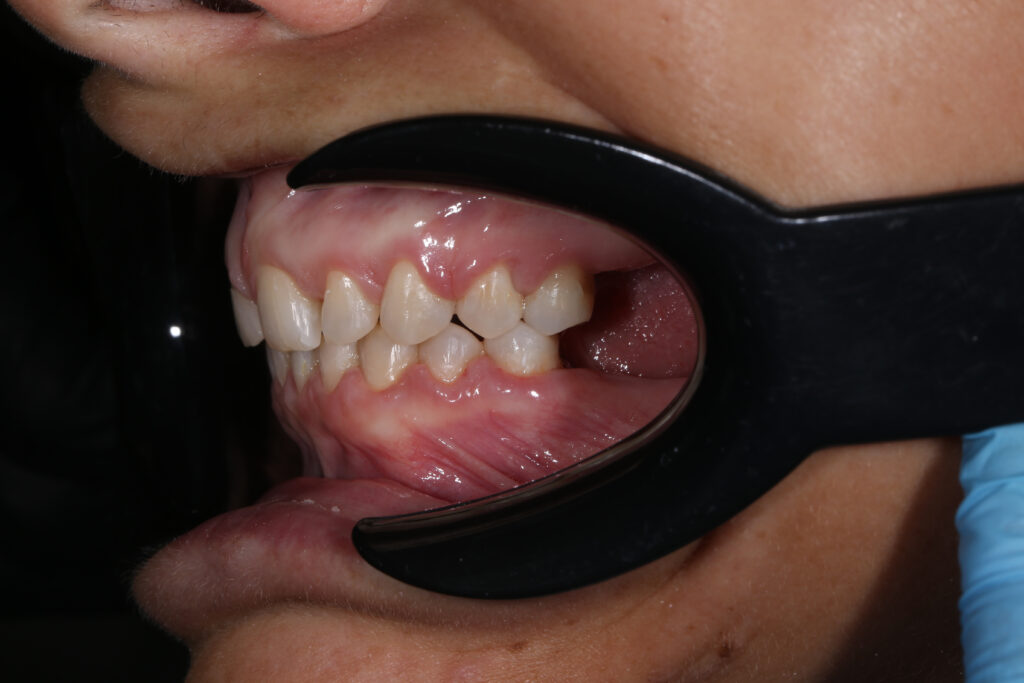

Результаты ортодонтической части

Была установлена брекет-система Damon Q. Срок лечения брекетами составил 11 месяцев.